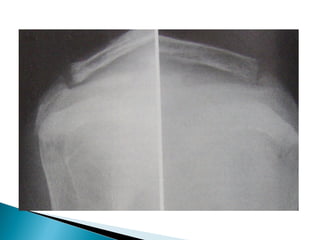

Osteoporosis • Subperiosteal cortical resorption of middle phalanges • Vertebral collapse • Brown tumors • Renal calculi,Nephrocalcinosis • Chondrocalcinosis

 Fracture neck of femur is common

 Fracture line is usually vertical at the base of the

neck with preexistent coxa vara